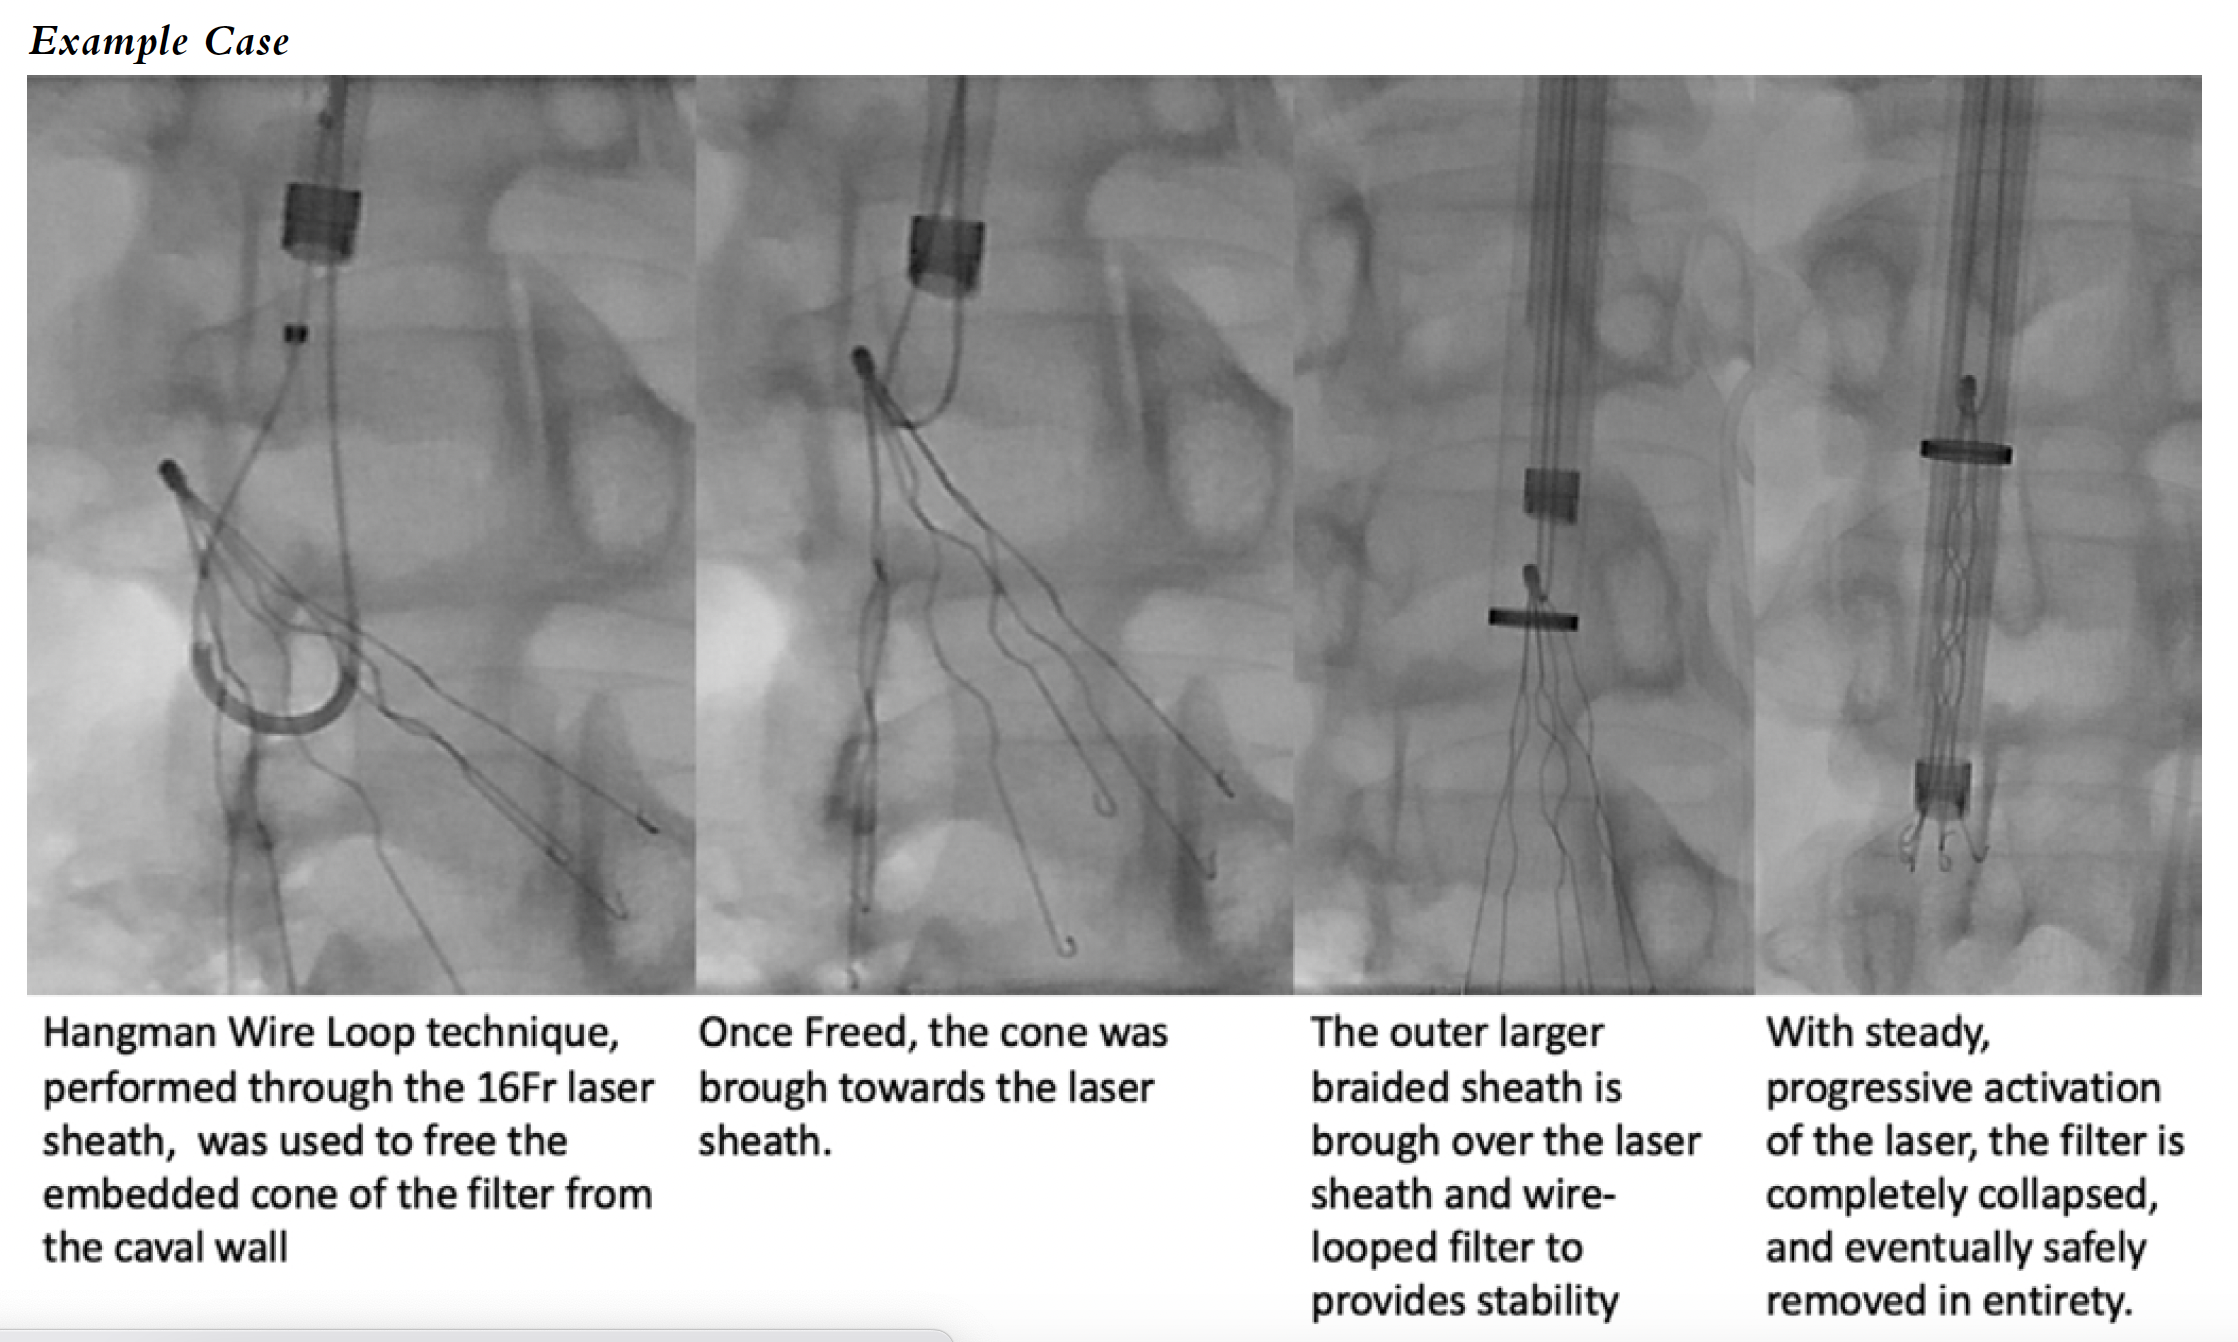

Wire Loop/Hangman Technique

The wire loop technique is used when a standard snare cannot grasp the hoop of a non-embedded filter. Using a reverse curve catheter that is guided through at least 2 filter struts, a hydrophilic wire is advanced cranially and the free end of the wire is snared and brought out of the sheath. Back tension on the wire loop is performed while the sheath is coaxially deployed to collapse the filter internally. It is important to perform oblique projections to ensure that the loop is not simply over a single strut, especially in filters that may have easily fractured struts, such as secondary struts in Celect filters (Cook Medical). Once confirmed, the continued tension, counter-tension technique between the loop wire and the sheath can help to safely collapse and remove the filter in its entirety.

The hangman technique is a modification of the wire loop technique when the hook/cone of the filter is embedded within the IVC wall due to formation of fibrin. In addition to the steps described above, considerably more continuous tension and counter-tension will be needed to gradually disrupt the fibrous capsule and successfully bring the proximal aspect of the filter into the sheath. Often, both techniques are used interchangeably.

Laser Sheath

Often, the amount of fibrin formation associated with the filter cannot be overcome with techniques such as wire loops and endobronchial forceps. Due to this, many advanced operators use laser-assisted filter removal, as the photoablative and mechanical qualities of the laser can release the filter from the caval wall. The CavaClear (Philips) IVC filter removal sheath is the first and only FDA-approved device for advanced filter removal, granted a De Novo designation in 2022. Prior to this, many operators utilized this device off-label, with considerable success. The CavaClear catheters come in 14 Fr and 16 Fr sizes and are used with the Nexcimer and CVX-300 laser generators (Philips). To use the laser catheter, first the hook, cone, or proximal aspect of the filter must be able to be brought into the sheath or catheter, either by using a snare, loop wire, or forceps. Often, the authors prefer to start with a 20 Fr sheath with a 16 Fr coaxial braided sheath, and attempt with the above-mentioned approaches to grab control of the filter. If, after having control of the top of the filter the attempt is not successful, the 16 Fr sheath is exchanged for the laser catheter, which can be advanced over a loop wire control. Once the laser is positioned over the top of the filter, whether it be conical or polyhedral, the laser is then activated in steady, short bursts, progressively advancing the catheter over time. Eventually the filter collapses and can be removed once it is completely within the catheter. An additional advantage of the laser sheath is that it has a metal tip, which can help disengage and remove the strut ends of filters that otherwise shred braided sheaths, such as the Greenfield filters. With growth of laser experience, permanent filters previously thought to be not removable have been removed, such as VenaTech LGM (B. Braun).6 With the recent FDA approval, it is likely that advanced interventionalists will often prefer to go straight to this approach when possible.